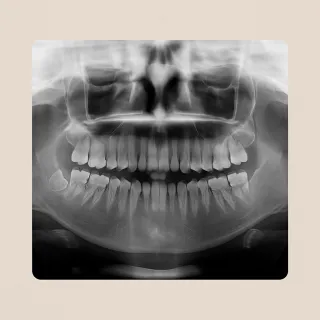

Yes! If you’ve had a recent panoramic X-ray or 3D scan (CBCT), just send it to us before your consultation.

It helps us give you a faster, more accurate treatment plan — and may reduce the need for additional scans when you arrive.

If you don’t have recent scans, don’t worry — we’ll take care of everything here with advanced imaging.